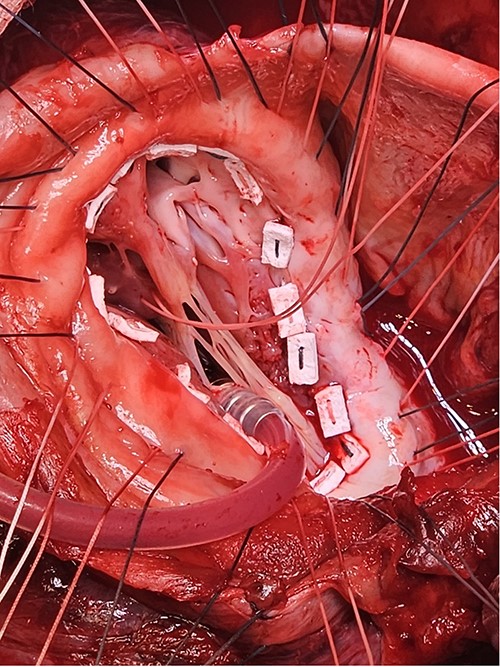

Following median sternotomy, cardiopulmonary bypass was instituted (bicaval drainage, ascending aortic return). Antegrade cardioplegia was delivered with aortic root venting and bicaval snaring. Dense adhesions surrounded the aneurysm, which had a thin wall, measured ⁓15 cm from LV apex to mitral annulus, and contained around 150 g of clot. The posterior mitral leaflet appeared retracted, preventing coaptation due to LV stretching. The aneurysm was resected (Fig. 2), and the LV wall repaired with a 5 × 3 cm patch, restoring normal LV size (Fig. 3). The musculotendinous junctions of the anterior and posterior papillary muscles were approximated using pledgeted 3–0 polypropylene sutures (Fig. 4). The patch repair was completed (Fig. 5), and the overlying sac oversewn for haemostasis.

A: The patch was parachuted down and secured. B: Following this the aneurysm sac was closed over the patch for added haemostasis.